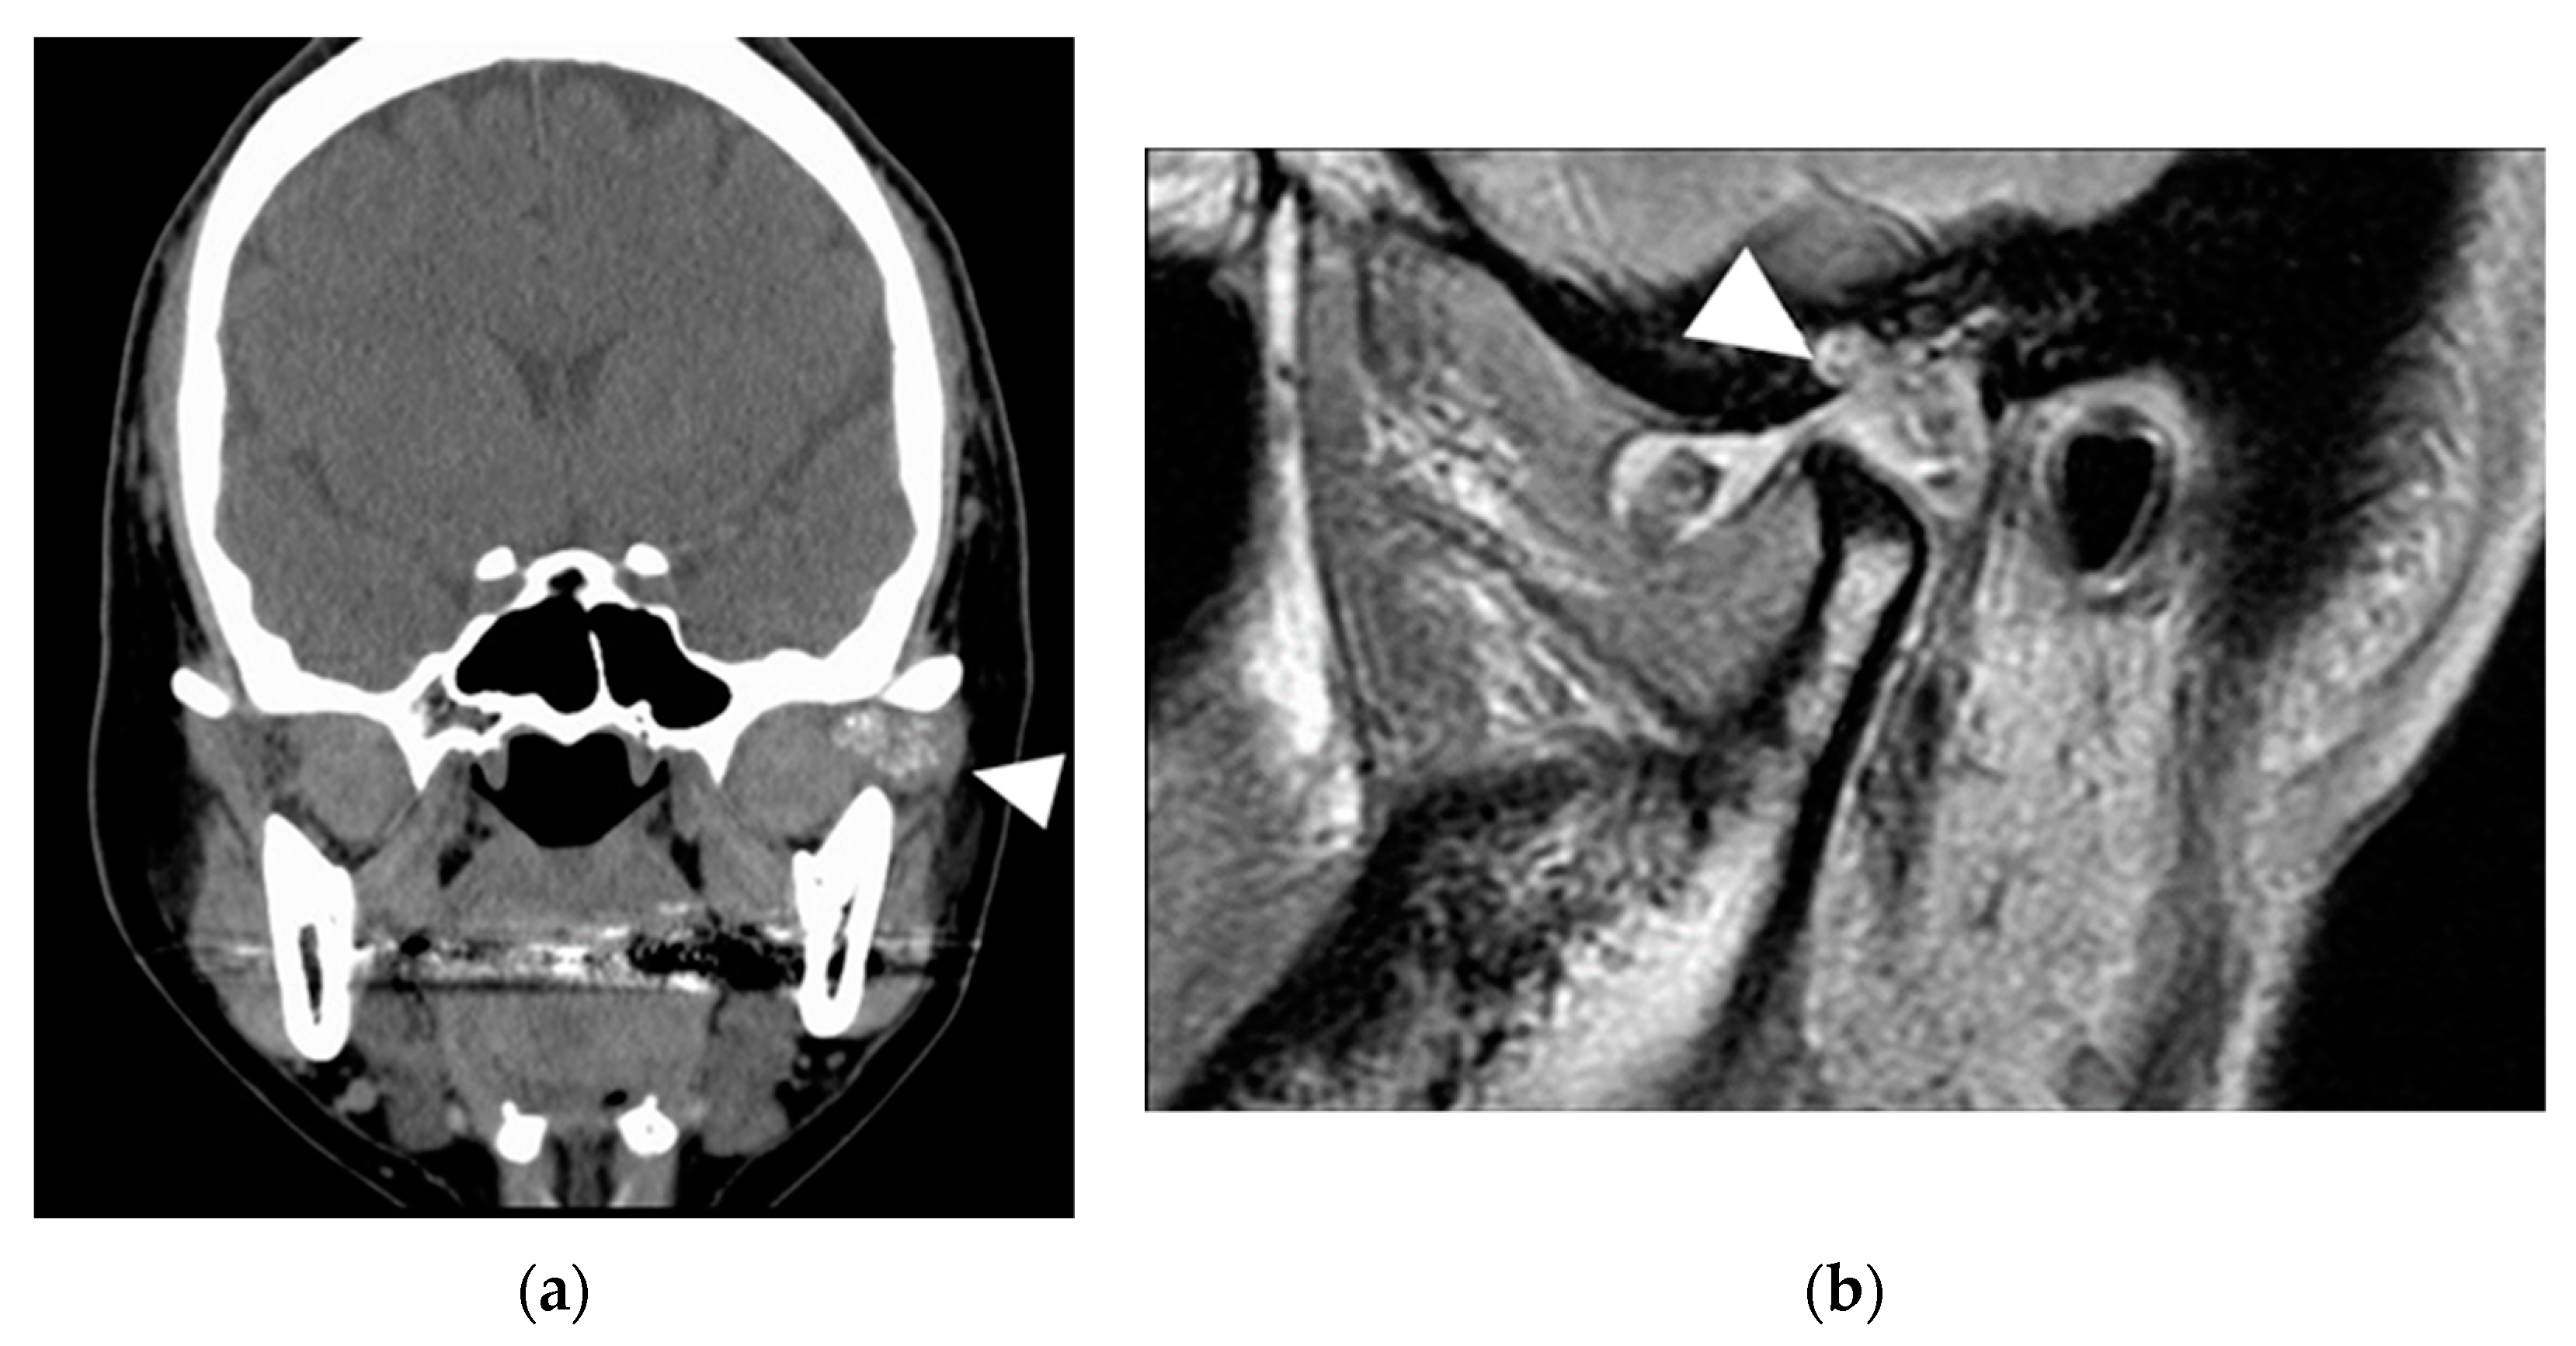

2.2. Patient 2